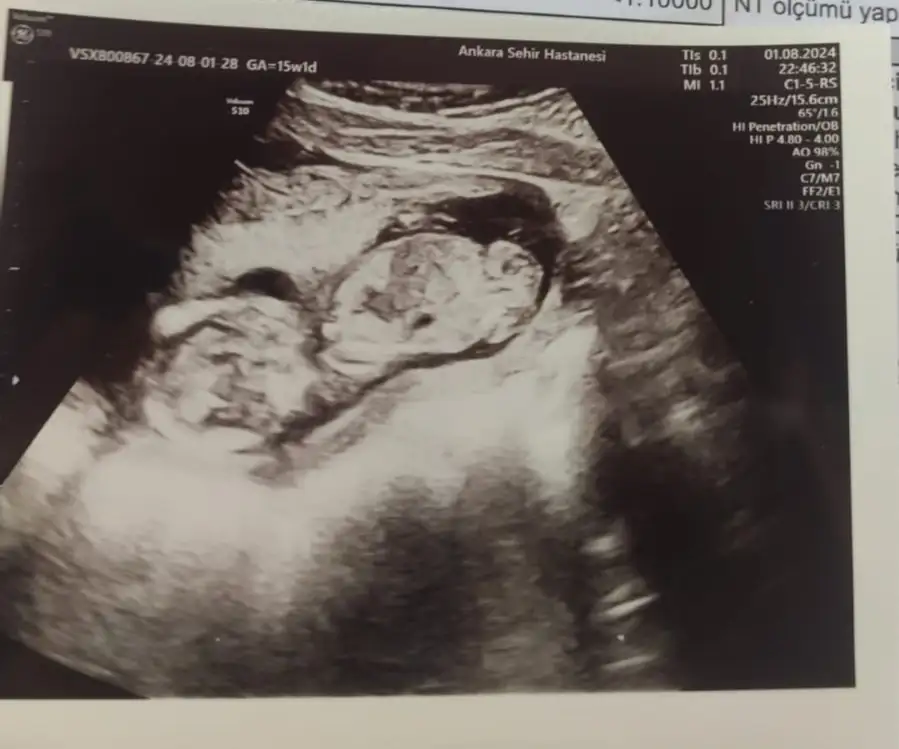

Kızlar öncelikle sağlıkla gelsin bebişlerimiz. Ben cinsiyetle alakalı bir şey sormak istiyorum. Baştan beri kız hissediyorum ilk bebegim ve 3 kez rüyamda kız gördüm. Hatta üçüncüsü çok netti suratını bile çizebilirim. Ama iki doktora gittim ikisi de erkek dedi 13-14. Haftada falandık sanırım. Şuan 16 olmak üzere. Acaba yanılma ihtimalleri var mı ben hala kız oldugunu hissediyorum rüyalardan dolayı kafam çok karışık.

Yanılma olabilir canım ben 12 haftada Medical park Keçiören hastanesinde çok iyi bi doktora gittim ve kesin erkek dediler ama ben hep kız hissediyorum hiç inanmadım 15.ve 17 haftada devlet hastanesine gittim ve bu bebek kız dediler kesinleşti kız olduğu Allah gönlüne göre versin inşallah